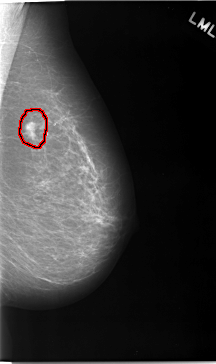

C_0046_1.RIGHT_MLO

LEFT_MLO LINES 5824 PIXELS_PER_LINE 3456 BITS_PER_PIXEL 12 RESOLUTION 50 OVERLAY

FILE: C_0046_1.LEFT_MLO.OVERLAY

TOTAL_ABNORMALITIES 1

ABNORMALITY 1

LESION_TYPE MASS SHAPE LOBULATED MARGINS SPICULATED

ASSESSMENT 5

SUBTLETY 5

PATHOLOGY MALIGNANT

TOTAL_OUTLINES 1

BOUNDARY